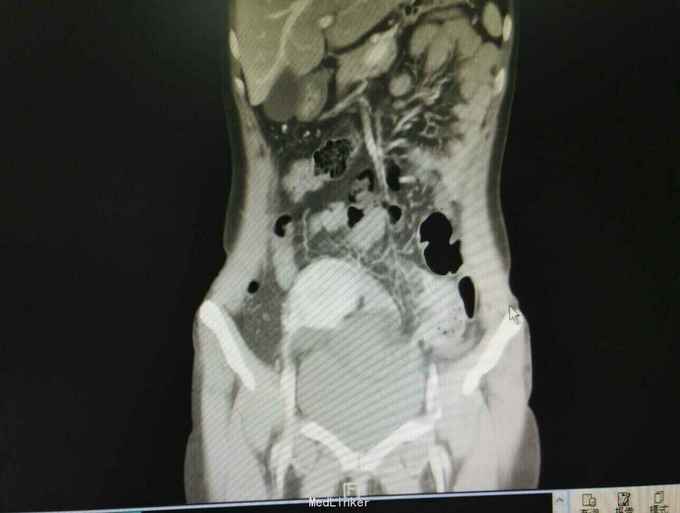

入院后急查血象稍高,完善急诊CT示内疝并闭袢性肠梗阻,予急诊行剖腹探查,术中见子宫右移,距离回盲部50cm回肠内疝入子宫与前腹壁所形成的黏连中,松解黏连,见回肠约15cm缺血坏死,予切除后吻合,缝闭黏连所造成的腔隙,关腹。术后常规治疗,患者回复可予出院。病理如图。

患者腹痛入院,各项生命体征平稳,无腹膜炎体征,抽血也没较大的异常,常规来说并不需要特殊处理,所幸的是完善了CT,及时发现了腹痛原因,因黏连形成的腔隙与腹腔隔离,所以患者腹痛不明显,即使肠坏死一般情况也无特殊,患者发病时间短,CT检查及时,避免了延误治疗导致肠坏死加剧。从中我们可以吸取教训,对于急腹症腹痛不典型的患者,不能用某种炎症解释病情的话,如果既往有手术病史,一定要注意内疝可能,对当前的医疗环境来说,急诊CT可以帮助明确诊断